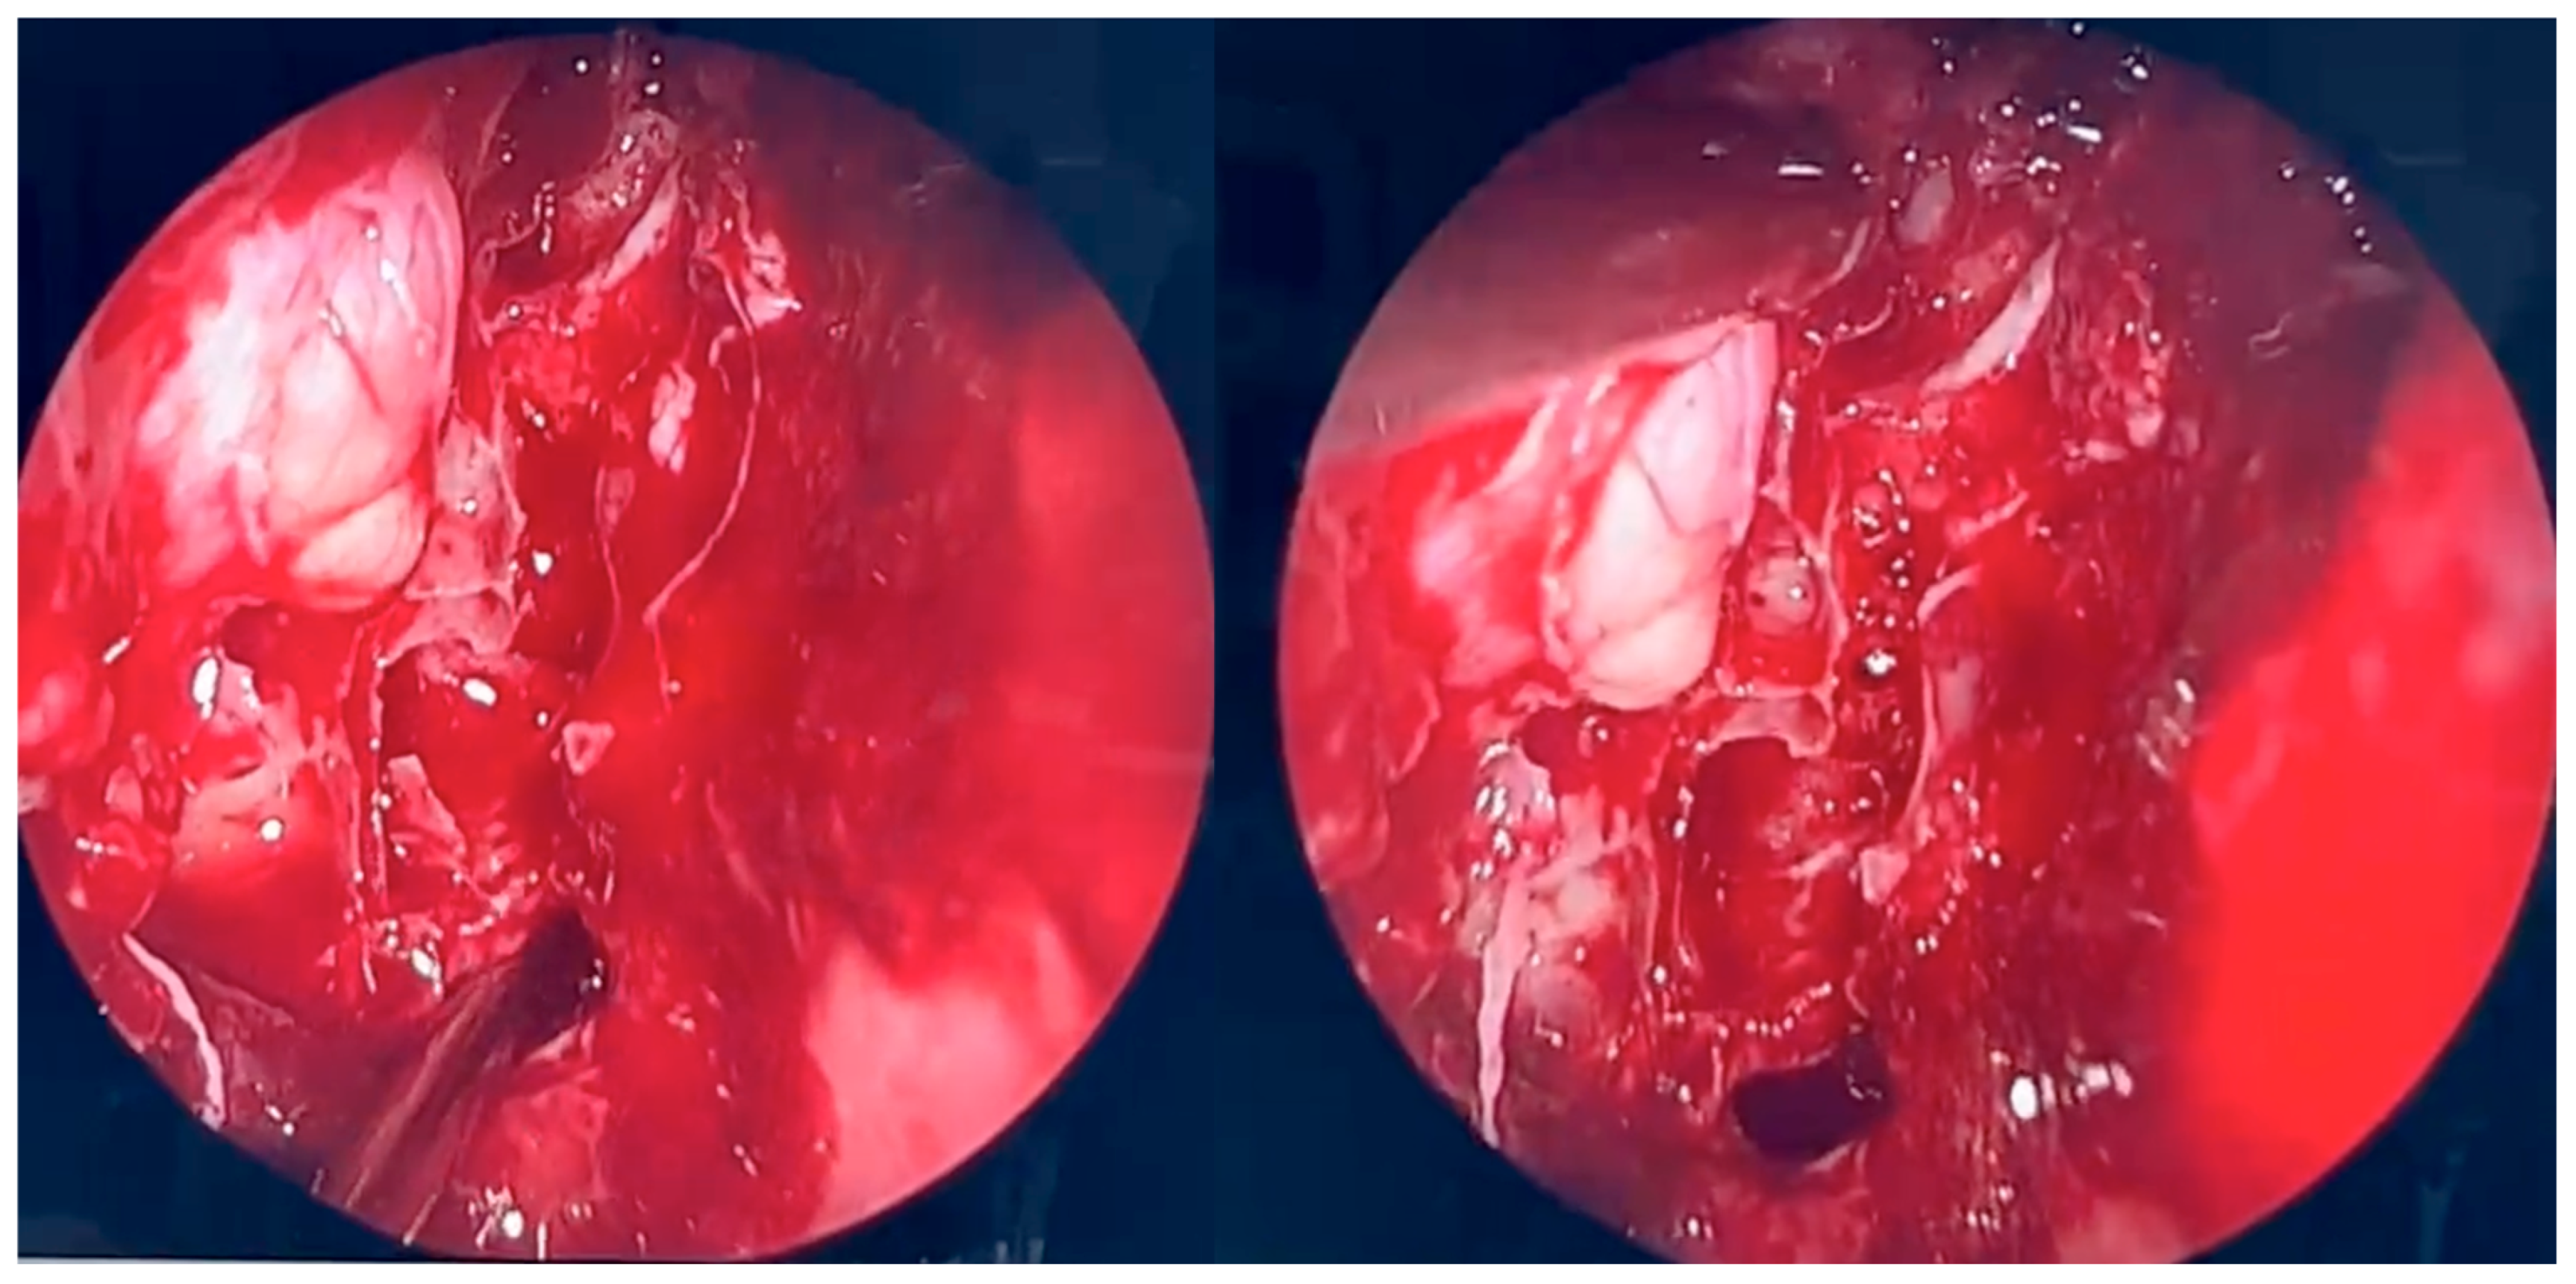

During the second endoscopic procedure, significant postoperative anatomical alterations were observed, including extensive scarring and multiple synechiae. A defect of the medial orbital wall was identified. The underlying bone was visualized and found to be covered only by periosteum. Using a diamond burr, a portion of the bony boundary of the frontal recess was carefully removed to create a surgical access route toward the lesion previously identified on CT and MRI imaging. The lesion was located in the superomedial quadrant of the right orbit, between the medial and superior rectus muscles and adjacent to the retrobulbar segment of the optic nerve. The orbital periosteum was incised, and orbital fat was gently displaced to access the lesion. The pathological tissue was successfully removed and sent for histopathological examination. A nasal dressing was applied to complete the procedure.

Figure 4. Endoscopic surgery: intraoperative view after removal of fungal infiltration to the level of the skull base. Opening of the sphenoidal sinus seen inferiorly (6 o’clock position). The upper-left part of the picture (11 o’clock position) shows the site of orbital periosteum incision with partial herniation of orbital fat into the ethmoid cavity. Two images obtained from the same projection.

Figure 5. Endoscopic surgery: intraoperative view of the right maxillary sinus after removal of fungal masses. Opening of the sphenoidal sinus visible on the right (4 o’clock position).